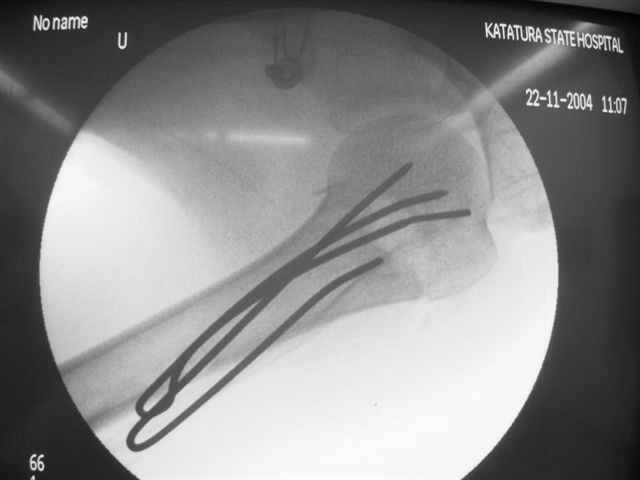

Женя, а как ты водишь спицы, в смысле, как делаешь входное отверстие, и как в него проводишь V-спицу? А то о дна из спиц, та, у которой не дошла до головки одна палочка буквы V, как-то выглядит на рентгенограмме, как будто или через очень большое отверстие введена, или каждая половинка через отдельные отверстия.

В чем ты видишь причину вторичного смещения?

Мне кажется, проблема в том, что не все концы спиц зашли в головку, и зашедшие - недостаточно далеко прошли.

С комментариями абсолютно согласен.

Спицы провожу по передней и задней поверхностям плечевой кости через 4,5 мм отверстия на разных уровнях.

Идеей презентации случая была демонстрация важности постоп Рг - хотя казалось бы все было сделано под флюороскопическим контролем и интраоперационно подозрений на нестабильность не возникло, а такая вот

неожиданность...

Уточни - обе части буквы V вводишь в одно отверстие? А то по снимкам выглядит, что в разные.

V-спица проводится через 4,5 мм отверстие. Видимо, из-за разной длины вторая половина спицы *пролетела* мимо отверстия, что и привело к вторичному смещению костных фрагментов.